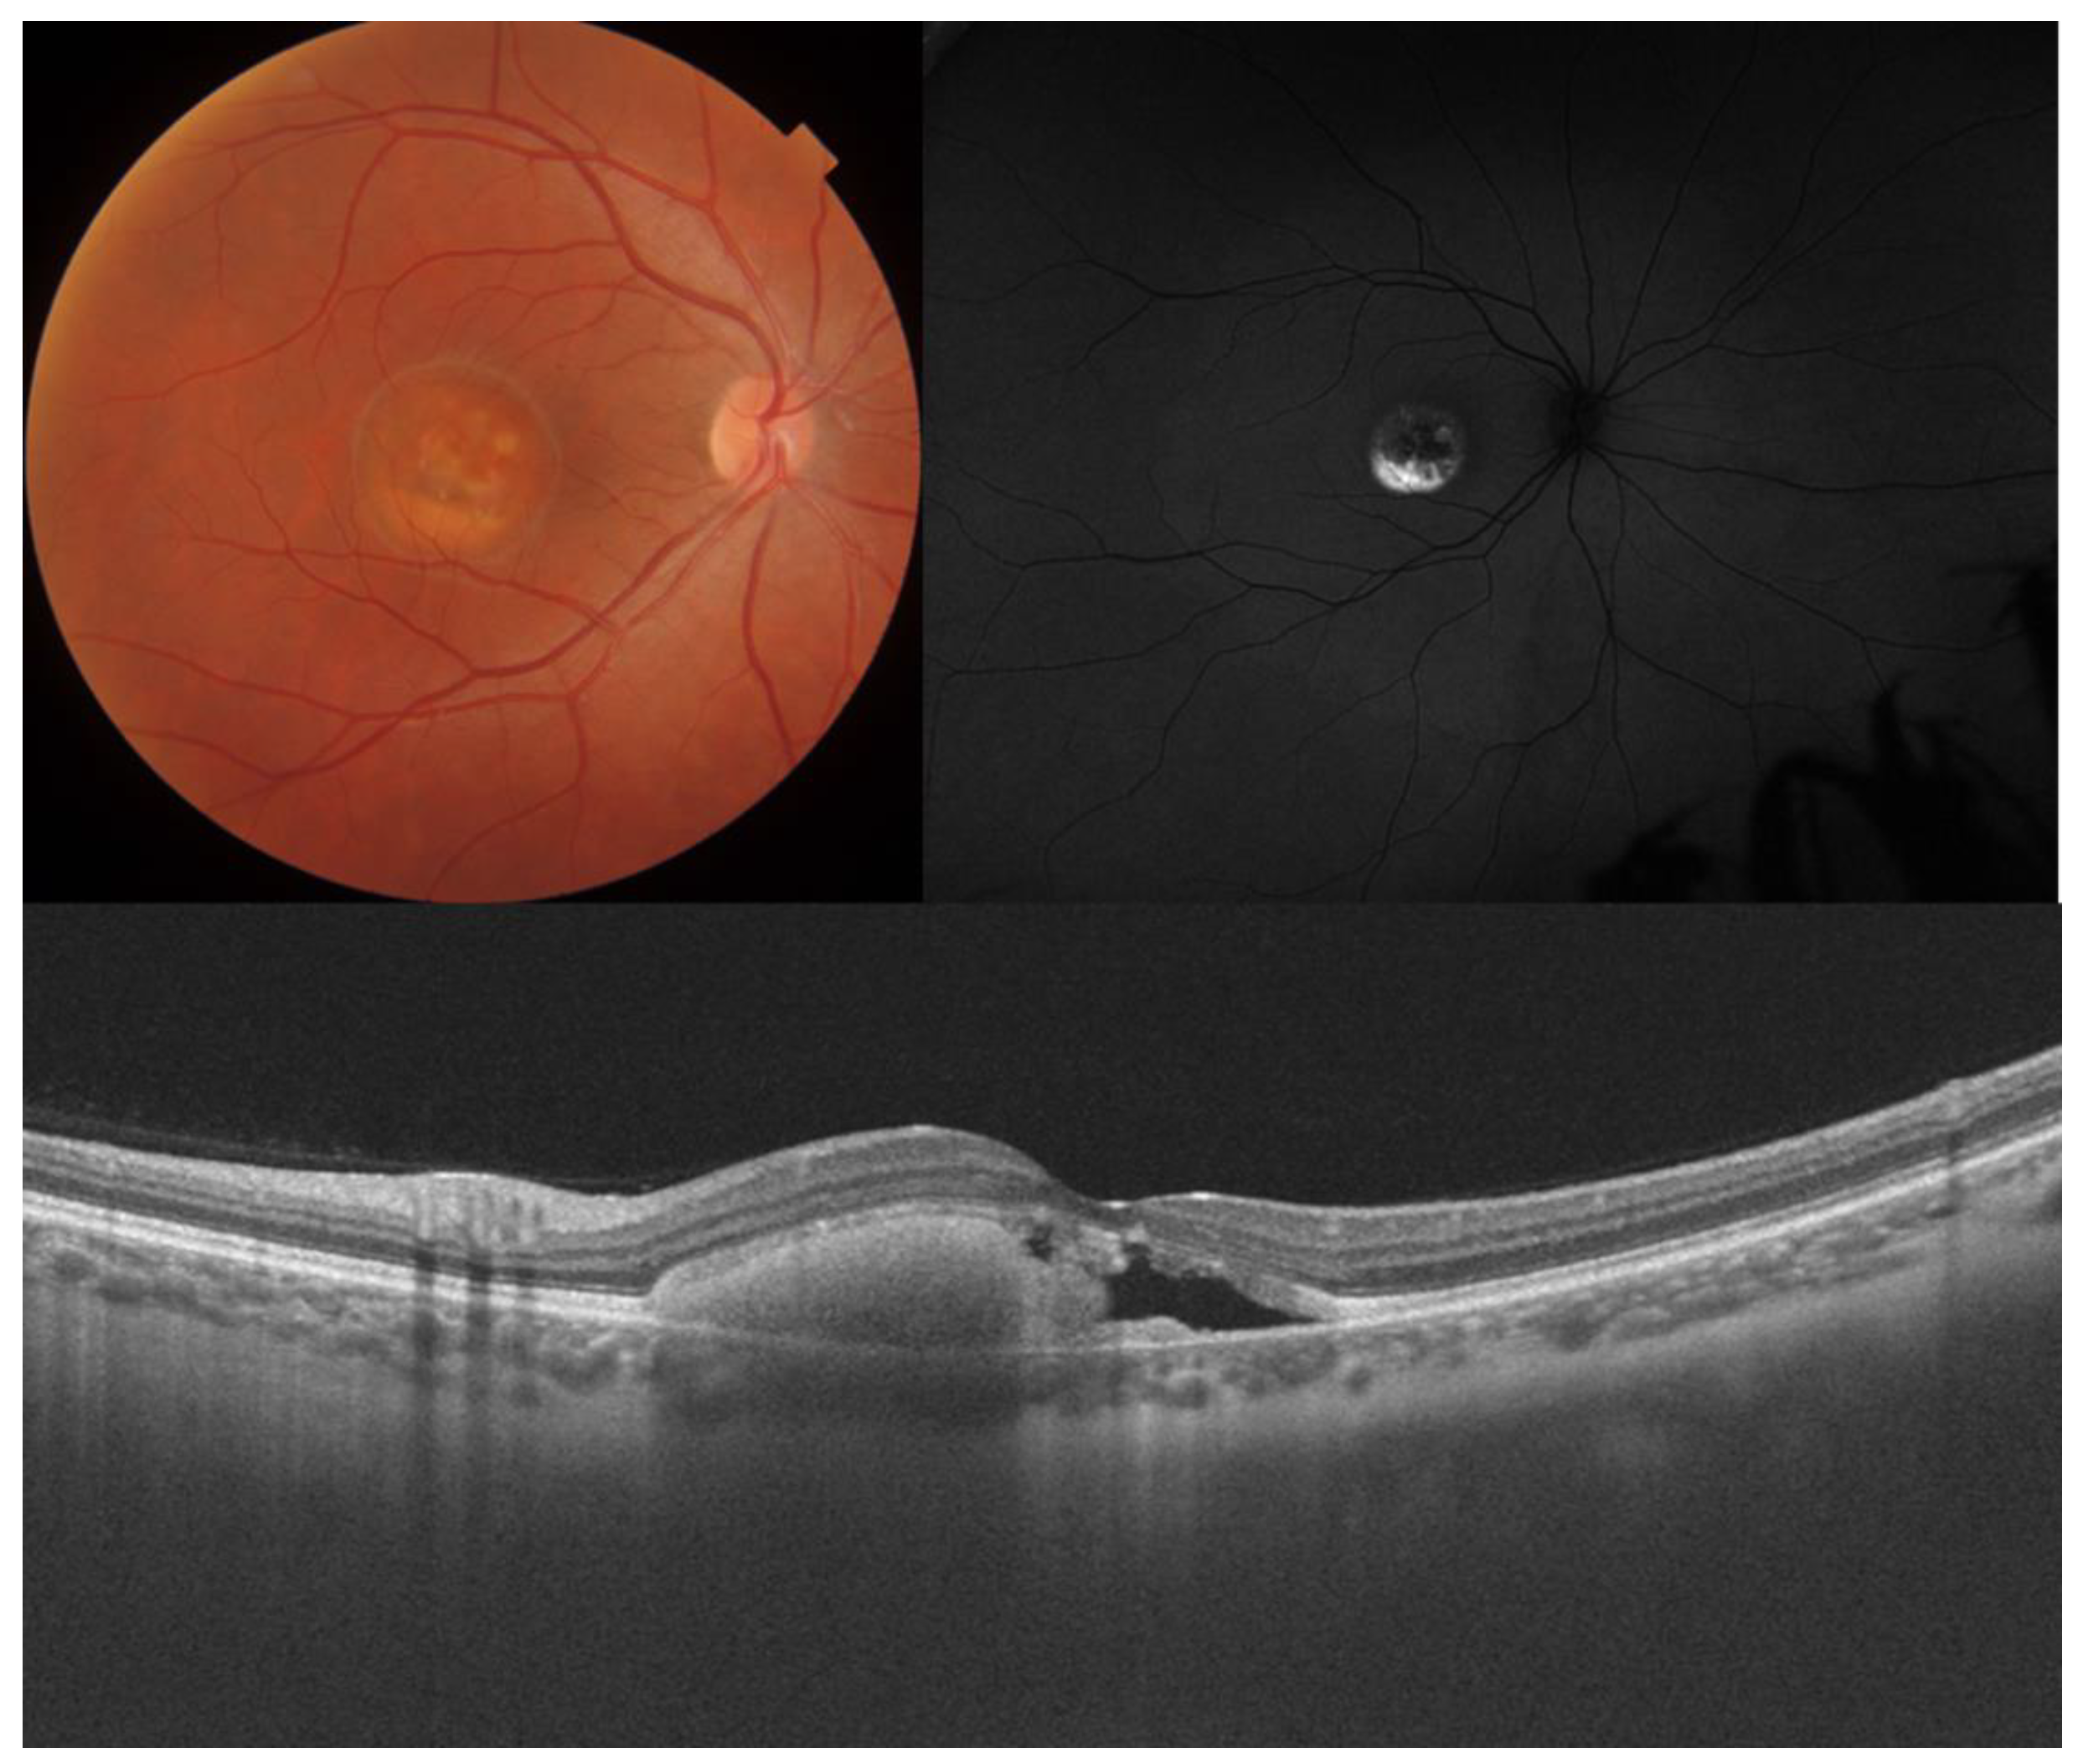

3. Best Vitelliform Macular Dystrophy

| Best vitelliform macular dystrophy |

|